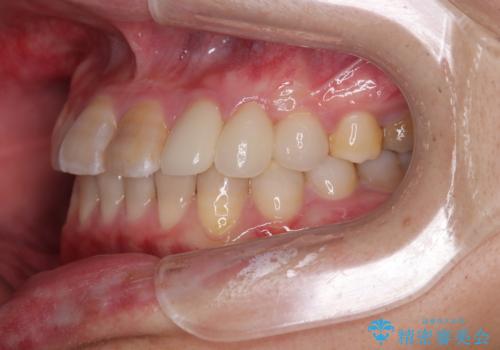

- 上下の前歯のデコボコを改善したいと来院された患者様です。

上顎の歯列幅が狭く、それによって歯が並ぶスペースが不足しています。

また下顎の歯列幅も制限され、内側に歯が倒れています。

上顎が側方に拡大されて歯が並ぶスペースを確保できました。

それに伴い下顎の歯列も拡大され、舌側に倒れているのが改善されました。